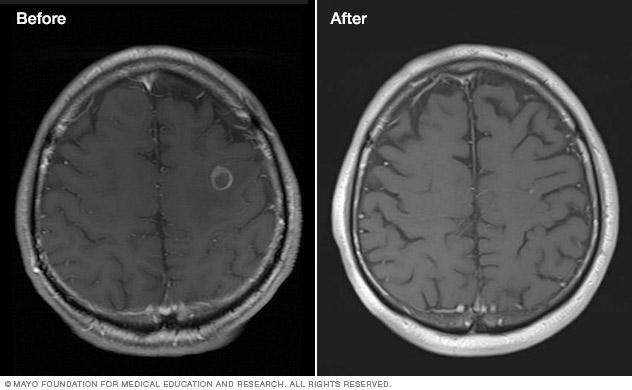

Brain tumor before and after treatment

Brain tumor before and after Gamma Knife treatment

Malignant brain tumor before (left) and 111 months after Gamma Knife stereotactic radiosurgery (right)

The treatment effect of stereotactic radiosurgery occurs gradually, depending on the condition being treated:

• Malignant tumors. Cancerous (malignant) tumors may shrink more rapidly, often within a few months.